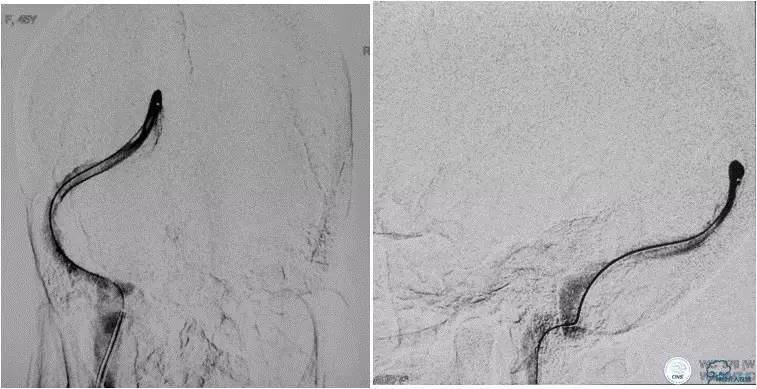

患者入院后,予以行脑动脉造影显示:右侧横窦和乙状窦交界区狭窄,左侧横窦和乙状长段重度狭窄(图3);经股静脉入路行右侧横窦和乙状窦测压显示狭窄两端压力差约为28 mmHg(图4)。遂予以阿司匹林100mg,每日一次,氯吡格雷75mg,每日一次。3d后在全麻插管下行右侧横窦-乙状窦交界处支架植入术。术中采用经右侧颈静脉入路,植入8~30mm 库克公司的ziliver支架,造影见右侧横窦-乙状窦交界处狭窄解除(图5),术中再次测压结果显示狭窄两端压力差约为1mmHg。术后自述双眼视物明显好转,但术后第3天眼底检查双视盘水肿较术前未见明显改善。

图4:经股静脉入路行右侧横窦-乙状窦狭窄处测压显示狭窄两端压力差为28mmHg。